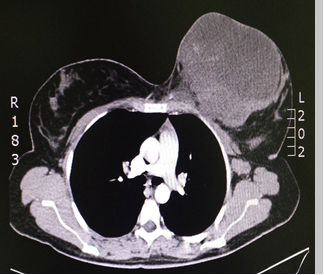

Ingresó al HPTU por dolor intenso en la mama asociado a fiebre. En la tomografía de tórax se observó una masa en la mama izquierda, de características neoplásicas, adherida a planos profundos, asociada a adenopatías pectorales y axilares (Imagen 2).